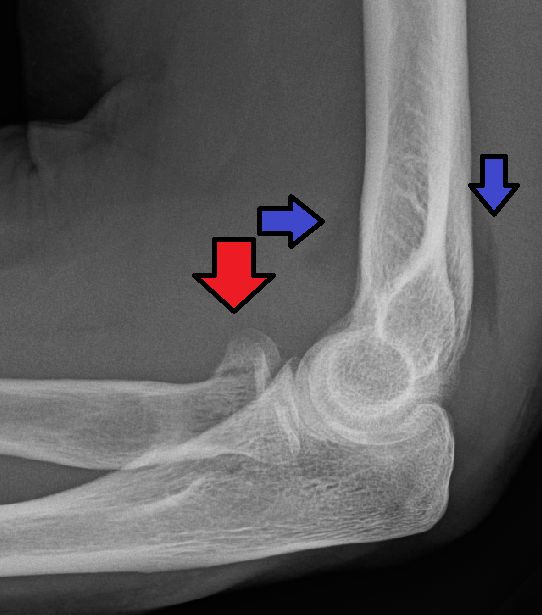

Xray

Xray (red arrow)

(blue arrow is for Fat Pad sign)